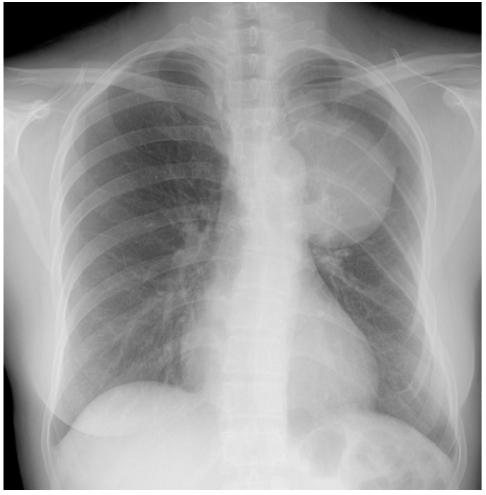

Figure 3

A chest radiograph showed a large mass in the left lung and a scoliosis.

A 41-year-old woman came to the hospital for the evaluation of a lung mass found on a chest radiograph. The patient had no signs or symptoms. However, on physical examination, widespread café-au-lait spots, cutaneous neurofibromas (Fig. 1A), axillary frecklings and reddish brown spots on the iris (Lisch nodules) (Fig. 1B) were present, consistent with the diagnosis of NF-1 [1]. Among the family members, a 14-year-old daughter and 12-year-old son had similar manifestations of NF-1 (Fig. 2). A large mass and a scoliosis were noted on a chest radiograph (Fig. 3). The chest CT and MRI (Fig. 4) showed a 7 cm homogeneous cystic mass with a thin wall in the left paravertebral area, extending into the spinal canal through the T5-6 neural foramen. Clear fluid was withdrawn by needle aspiration and the diagnosis of an intrathoracic meningocele was made. Regular follow-up with periodic imaging was recommended without surgical treatment.